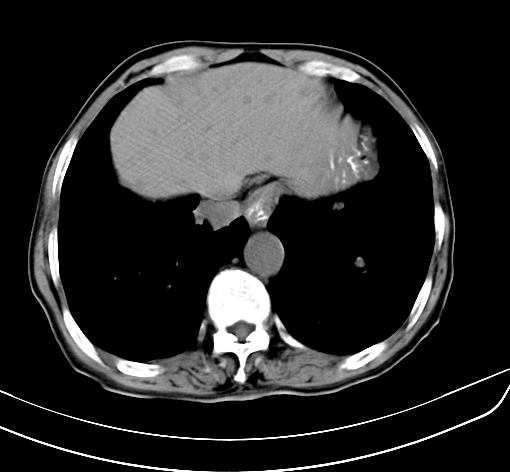

病人 男 70 咳嗽 胃部不适 2月余

胆囊壁增厚,与临近肝实质边界不清,临近肝实质内可见大片边界不清之低密度区,肝门区密度亦有减低,部分结构不清,尾叶前方可见块状影,肝右叶可见多枚边界不清之圆形低密度区,肝内胆管扩张征象,结合病史考虑1胆囊癌肝内转移,肝门区淋巴结转移,门脉癌栓待排2肝内胆管扩张3建议增强扫描

肝脏多发大小不等低密度灶,边界不清,肝门区结构不清,肝内胆管轻度扩张,胆囊密度不均匀,内见软组织样密度影,与相临肝脏边界不清.考虑:1、胆囊ca侵犯肝脏并肝内多发转移,肺上也有结节影,转移?建议强化扫描.2、胃充盈不好,如怀疑有病变最好建议做相关检查.

胆囊壁增厚,周围模糊不清,肝内多发低密度影,胃充盈欠佳,胃壁增厚,外形尚规整,考虑胆囊炎、胆囊癌肝内转移?建议胃肠道进一步检查或增强扫描。